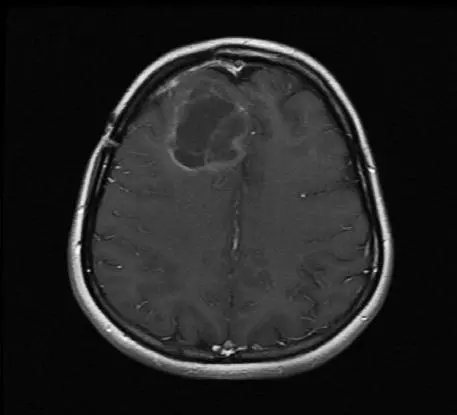

Исследования с вирусом полиомиелита на данный момент ведутся в основном на пациентах с продвинутой стадией глиобластомы – одного из самых смертоносных и агрессивных видов рака мозга, который часто убивает через несколько недель после того, как все стандартные способы лечения перестают работать. Ученым удалось продлить жизнь нескольких пациентов на месяцы и даже годы [9].

Энцефалограммы 20-летнего студента, которого лечат модифицированным вирусом полиомиелита (PVS-RIPO), вводимым через катетер, подсоединенный прямо к опухоли.